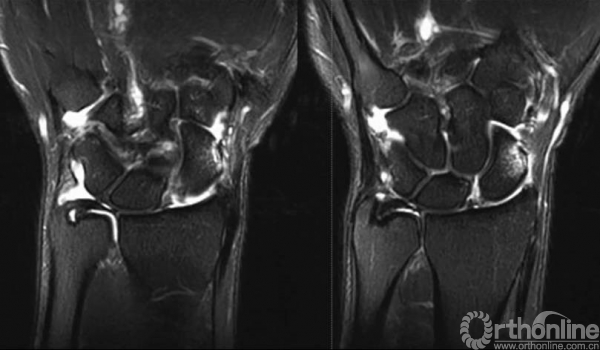

MRI可见舟月韧带撕裂。